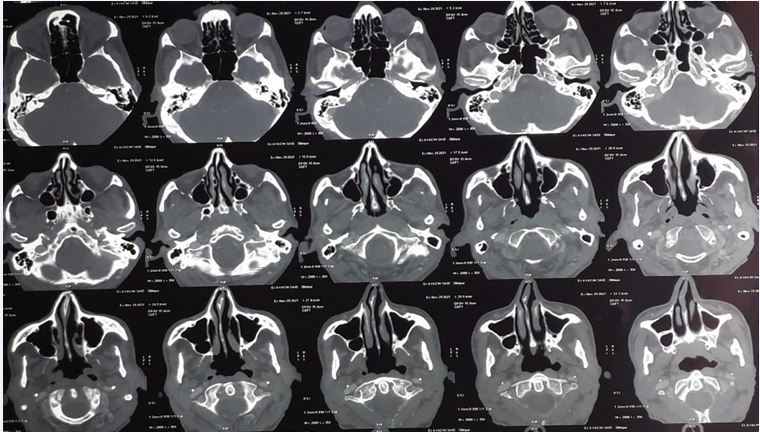

Due to the abnormal appearance of the nasal cavity, a sinus CT scan and a naso-rhino- cavoscopy with biopsy were performed (Figure 2).

Figure 2 CT images of the sinuses showing left septal thickening without signs of maxillary sinusitis

Imaging showed left septal thickening without signs of maxillary sinusitis, while endoscopy revealed a budding tumor in the left middle turbinate. Mycological (direct examination and culture) and bacteriological tests were negative. Histopathological analysis demonstrated chronic inflammatory and hemorrhagic changes with no specific features and no evidence of malignancy.